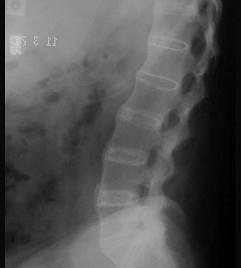

问题 男,21岁,下腰不适,晨起加重半年余,X线检查如图,请选出最可能的诊断 ( )

选项 A、化脓性脊柱炎 B、阻滞椎 C、脊椎退行性变 D、强直性脊柱炎 E、类风湿关节炎

答案 D